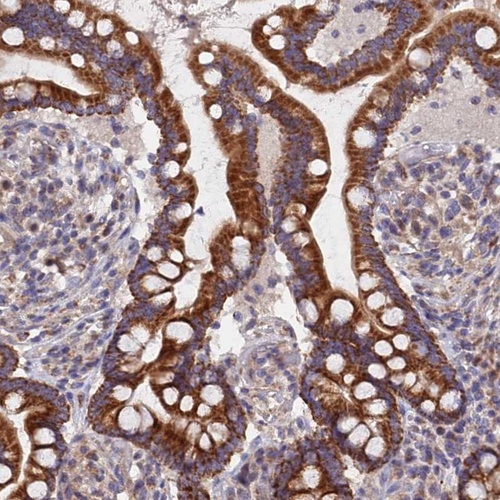

Immunohistochemical staining of human skeletal muscle shows strong cytoplasmic positivity in myocytes.